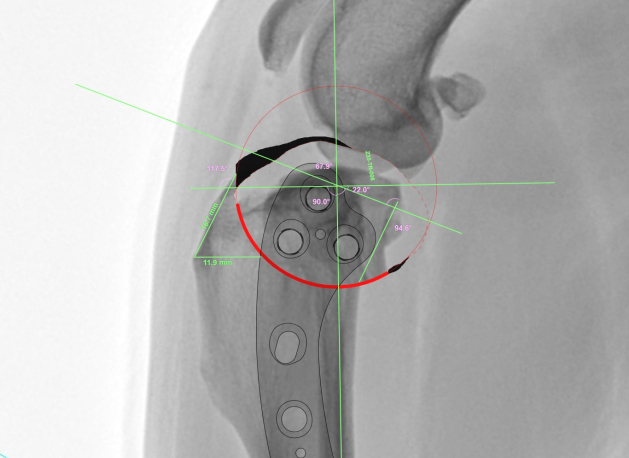

04수술 전 각도 조정수술 전, 정확한 각도 조정 수술 계획을 수립합니다.

-